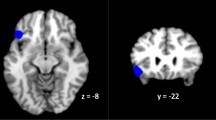

Given the well-documented link between ruminative thought and subgenual ACC activation (for reviews, see Hamilton et al., 2015; Nejad, Fossati, Lemogne, 2013), exploratory analyses were conducted to determine whether this region was activated to a greater extent among rMDD adolescents than among HC adolescents during rumination versus distraction, utilizing an uncorrected p value. Within the BA 25 mask from the Wake Forest Pickatlas, and using uncorrected thresholds of p < .05 and k > 15, rMDD adolescents exhibited greater activation during ruminative thought than did HC adolescents (Z = 3.55, p < .0002, k = 178, {–4, 4, 10}; see Supplementary Fig. 1).